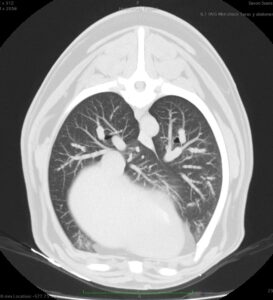

A los 18 meses del diagnóstico, los cuidadores refieren la aparición de hifema y exoftalmia en el ojo derecho, lo que sugiere metástasis, además de una masa perianal compatible con neoplasia indiferenciada (posible melanoma amelanótico). En el estudio de TC se documenta una respuesta completa de la lesión primaria y metástasis nodales y una remisión casi completa de las metástasis pulmonares (lesiones milimétricas equívocas) (imagen 1). Se realiza la resección de la masa perianal, pero los cuidadores rechazan la enucleación.

A los 28 meses se realiza un TC de re-estadiaje antes de considerar el segundo protocolo de radioterapia, donde se documenta una progresión objetiva de la masa oral y ligera progresión de la metástasis pulmonar (imagen 1).